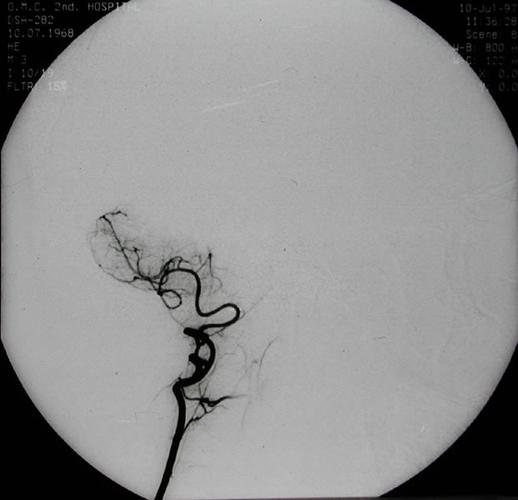

椎动脉造影

椎动脉

椎动脉图片